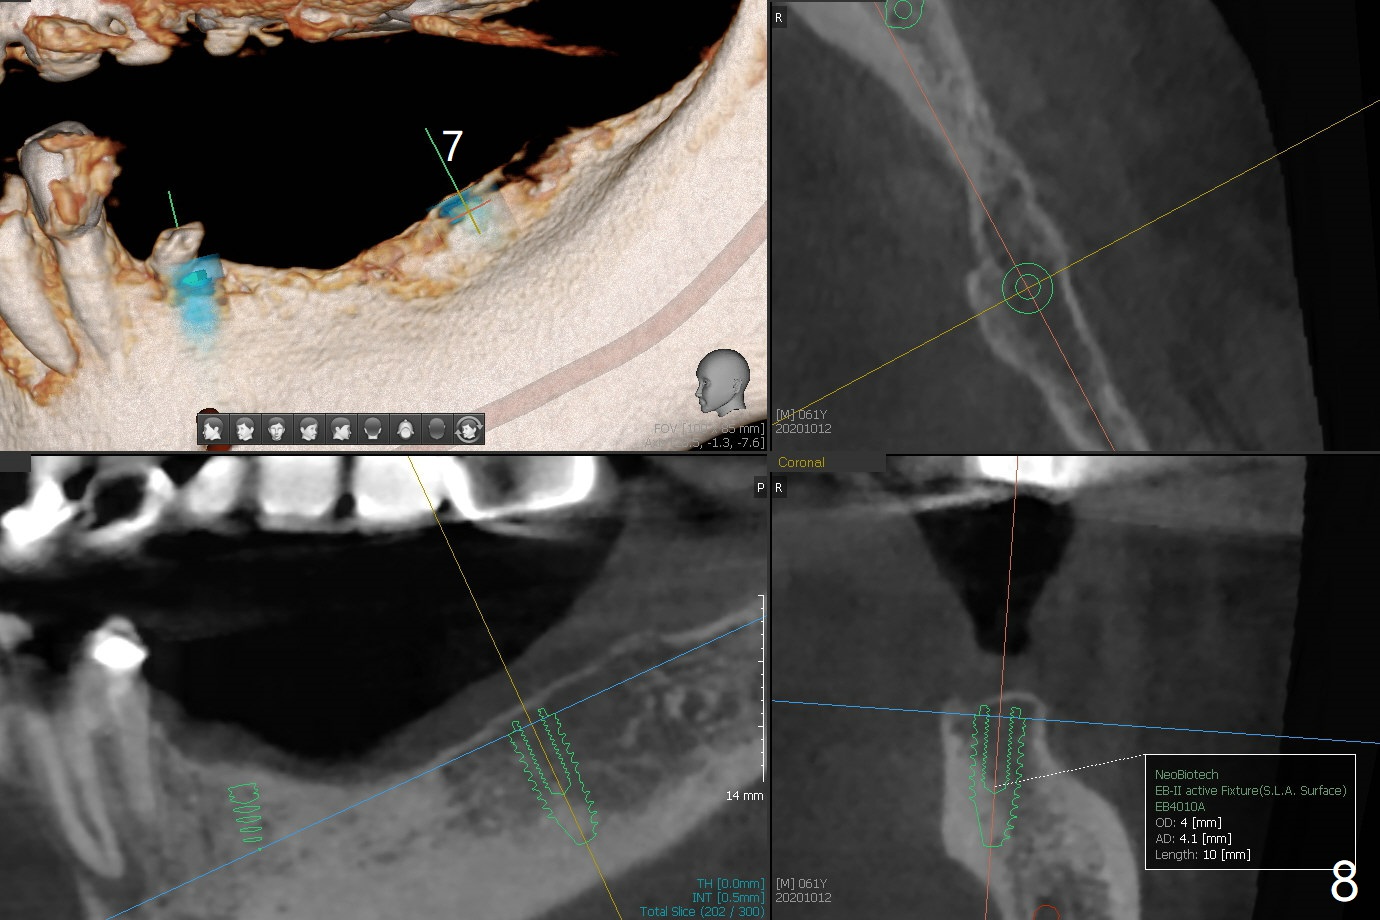

61男牙齿不好,左上4-8牙桥松动(图一,五,六),右下2,左下3根尖瘘道(图二),左上4,8也需要根管治疗,以上牙齿以及右下3插入球状牙桩(图一:*),然后在右上,左下,右下7植牙,放置球状基台(图一:箭头),固定上下活动义齿(覆盖义齿)。下前牙颊侧骨板几乎没有(图七)。左下7骨头(图八)宽于左下5(图三)。